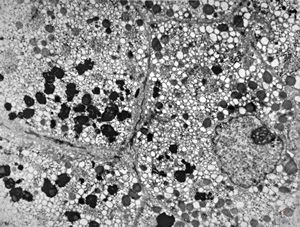

M,1y. | glycogenosis type I.(glycogen dissolved due to UA blockstaining)

F,1y. | glycogenosis type II.(glycogen dissolved due to UA blockstaining)

F,1y. | glycogenosis type II. (glycogen dissolved due to UA blockstaining)